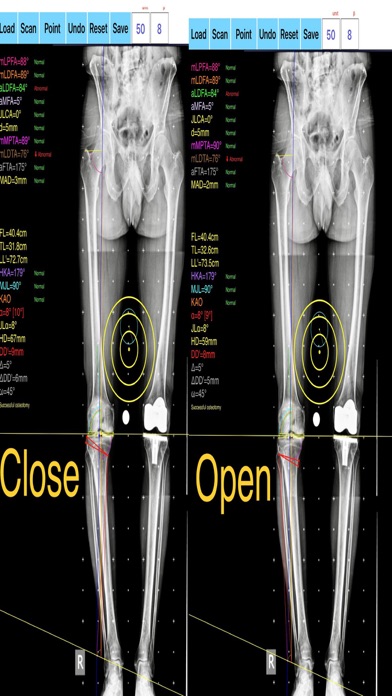

-the amount of correction preoperatively by calculating the dimension of  wedge size , the correction angle and osteotomy gap opening or closing.

-mechanical axis deviation (in mm) MAD, anatomical and mechanical femoral axes angle (aMFA),mechanical lateral proximal femoral angle (mLPFA), mechanical lateral distal femoral angle(mLDFA), joint line convergence angle (JLCA),mechanical medial proximal tibial angle (mMPTA), Mechanical lateral distal tibial angle (mLDTA), Hip Knee Ankle line (HKA) ,Mid joint line (MJL) orientation.

-objectively the deviation or deformity in the frontal plane (varus or valgus) and differentiate the level of deformity (femoral and or tibial origin) and according to measured angles objectively suggest where indicated, medial or lateral, open or closed-wedge distal femur osteotomy or high-tibial osteotomy or double osteotomies  and avoiding unwanted obliquity of the joint line

-evaluate in real time the success of intended osteotomy by evaluating the kinematic alignment of the knee (KAO), avoiding residual joint obliquity or malalignment.

-pressing + or - button, one degree of correction is added or subtracted respectively and the second plane of osteotomy emerges and printed in screen real offering real time simulation of the wedge osteotomy in an instant to comprehend in real time what parameters are affected and modify favourably the correction angle. All above mentioned angles and all limp axes are redrawn and updated accordingly for the given new correction angle. The drawn schematic gives the impression of settings  act as a whole interchangable interacting unit.